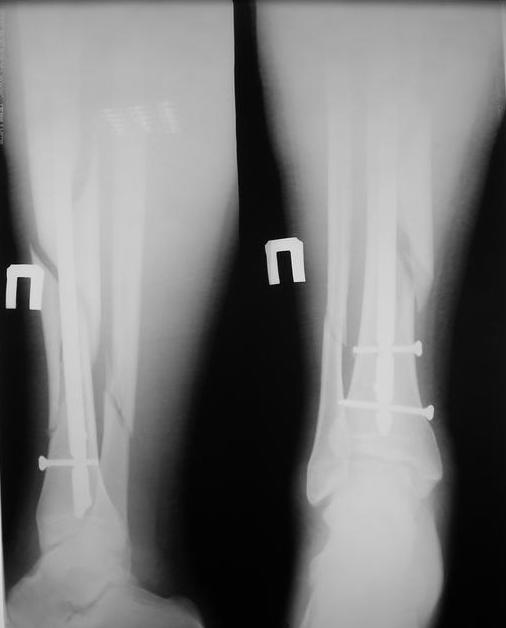

Уважаемые коллеги травматологи подскажите как нам быть и что делать. Думали всем отделением.Несращение оскольчатого перелома костей голени после интрамедуллярного блокируемого синтеза.

У нас был молодой пациент М.(26лет), травма 25 января 2009г, катался на лыжах и получил травму. Поступил к нам в отделение в экстренном порядке. При обследованиии выявлен закрытый винтоообразный оскольчатый перелом правой большеберцовой кости и косой перелом малоберцовой кости на границе средней и нижней трети. Выполнен интрамедуллярный блокируемый синтез большеберцовой кости, оси и длина конечности восстановлена. После операции пациент ходил с полной нагрузкой. Через 3 месяца на контрольных рентгенограммах сращения нет, динамизации не выполняли, так как оскольчатый перелом.(снимки в динамике прилагаются). Посоветуйте, что в данном случае делать наиболее целесообразно?

Остеосинтез, похоже, сделали с перерастяжением, так что динамизировать, наоборот, надо было еще и раньше обычного, недели через 4 после операции.

Да есть диастаз, но скорее от смещения осколка по ширине, а не по длине - по малоберцовой длина нормальна.

>Да есть диастаз, но скорее от смещения осколка по ширине, а не по длине - по малоберцовой длина нормальна

И малоберцовая перерастянута. По большеберцовой видно щель по переднему контуру, промежуточный фрагмент к этой области не имеет отношения.

мы бы подождали с динамизацией еще 6-8 недель

Отсутствие уверенных признаков сращения неделям к 8 - надо динамизировать. Тут уже 3,5 мес., есть щель из-за смещения по длине. Дальнейшее консервирование ситуации тут не решает никаких проблем, а вот создать их может. Динамизация с нагрузкой и диастаз уменьшит, и репаративный процесс "освежит".